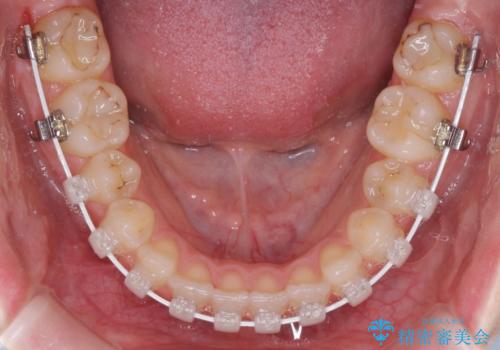

- 矯正装置

- ハーフリンガル

- 前歯のデコボコと八重歯を気にして来院された患者様です。

目立たない装置を希望されたので、上顎が裏側装置のハーフリンガルを選択し、左右上顎小臼歯1本ずつを抜歯して、矯正治療を行うこととしました。